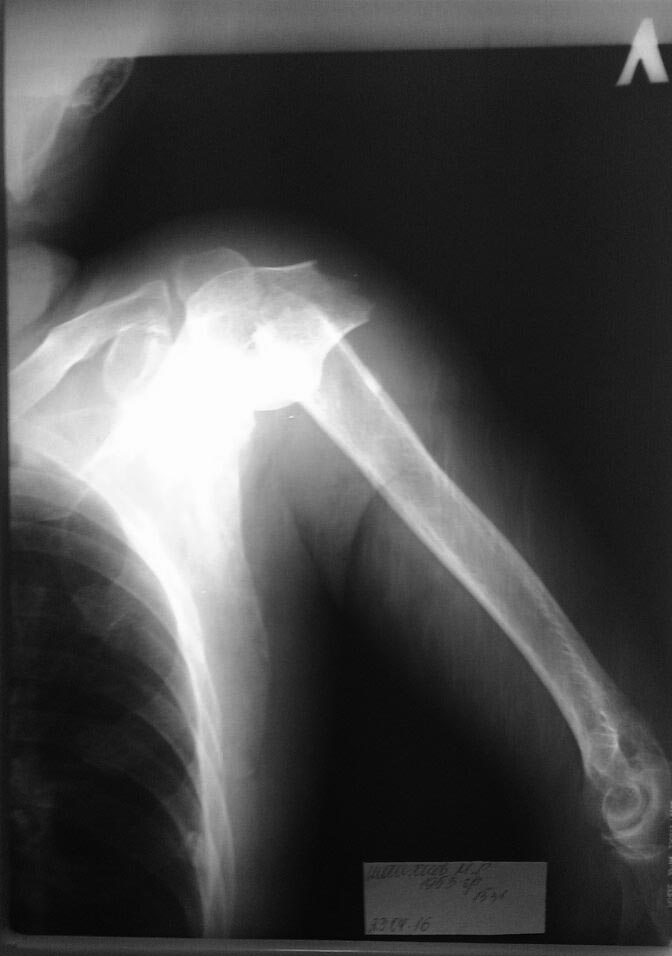

Больной х.1953гр поступил 23.04.2016 с диагнозом "закрытый перелом

хирургической шейки плечевой кости 10дневной давности".

Обширная подкожные гематомы в обл. плечевого сустава и шеи, грудной клетки.

Наложена гипсовая повязка на фото.

Планируется опер. лечение с пластиной лист клевера.